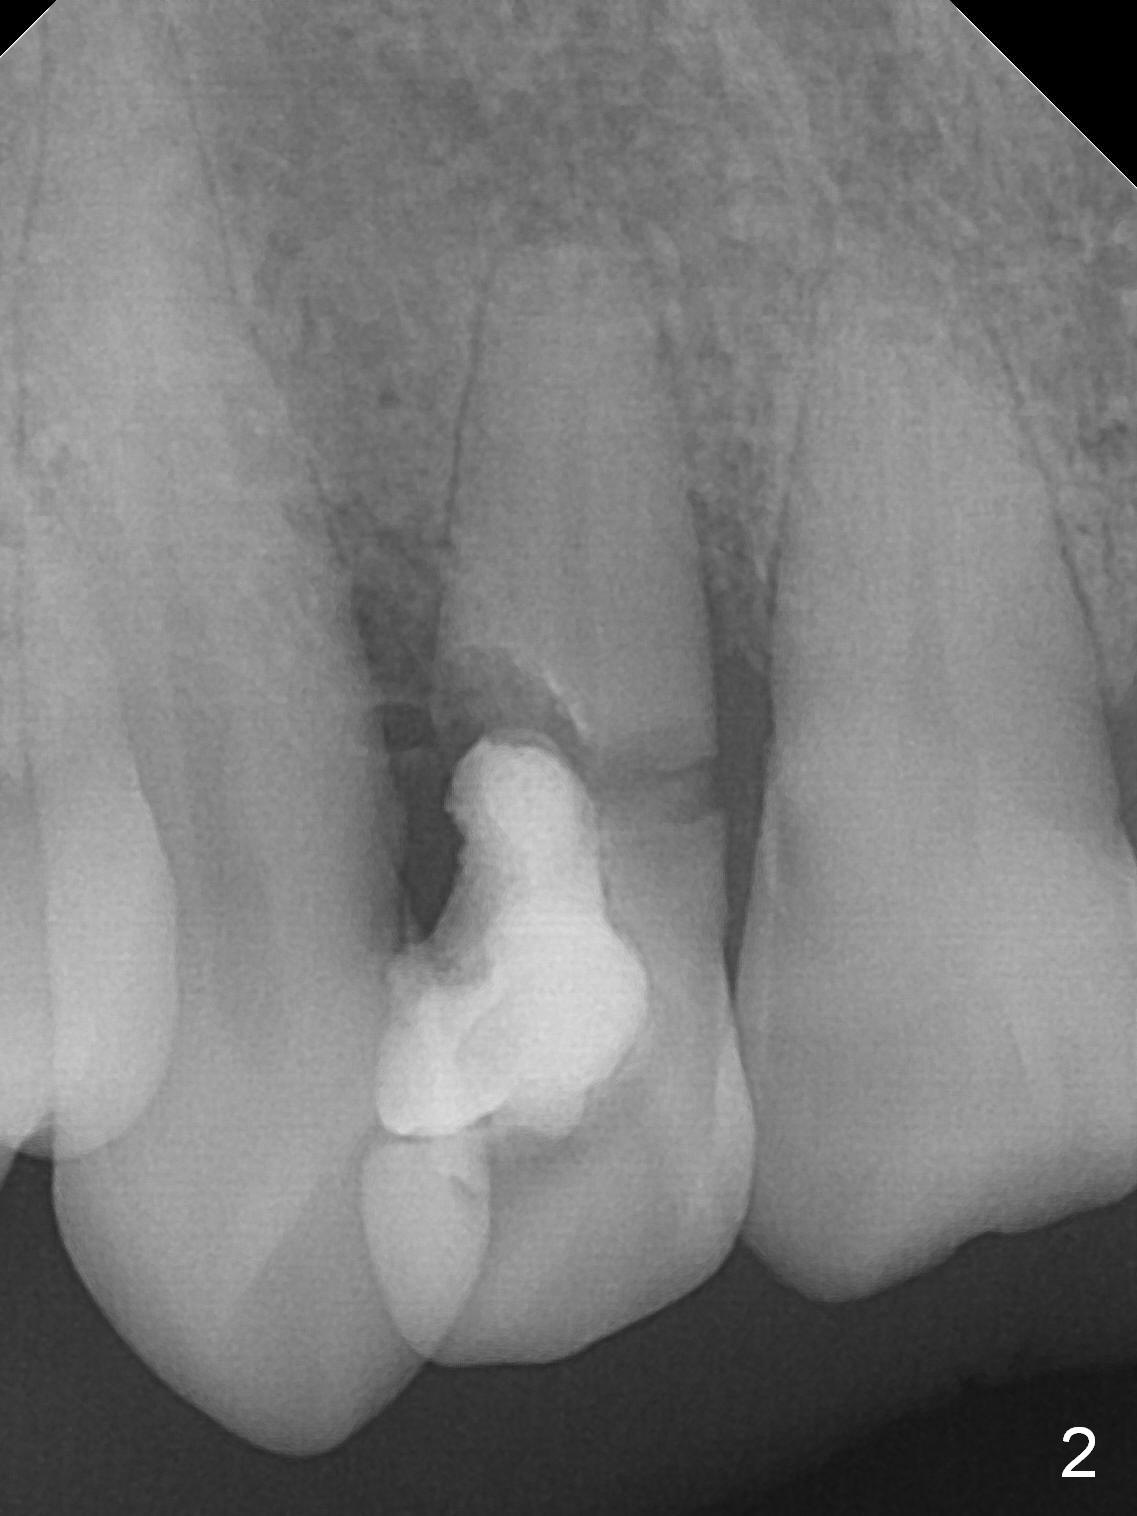

A 52-year-old man had a non-restorable lateral incisor 3 years ago (Fig.1). It fractures lately (Fig.2) with a buccal abscess (Fig.3 *) ) and fistula (>, possible severe buccal plate defect, prepare PRF). Severe deep bite (Fig.4) and malocclusion (Fig.5) will present a challenge to implant provisional restoration.

If the deep bite is a problem, place a healing abutment or the immediate provisional without the palatal apical wall. Or ask the patient in advance whether the right lateral can be placed as labial as the tooth #10 or not (Fig.3-5).